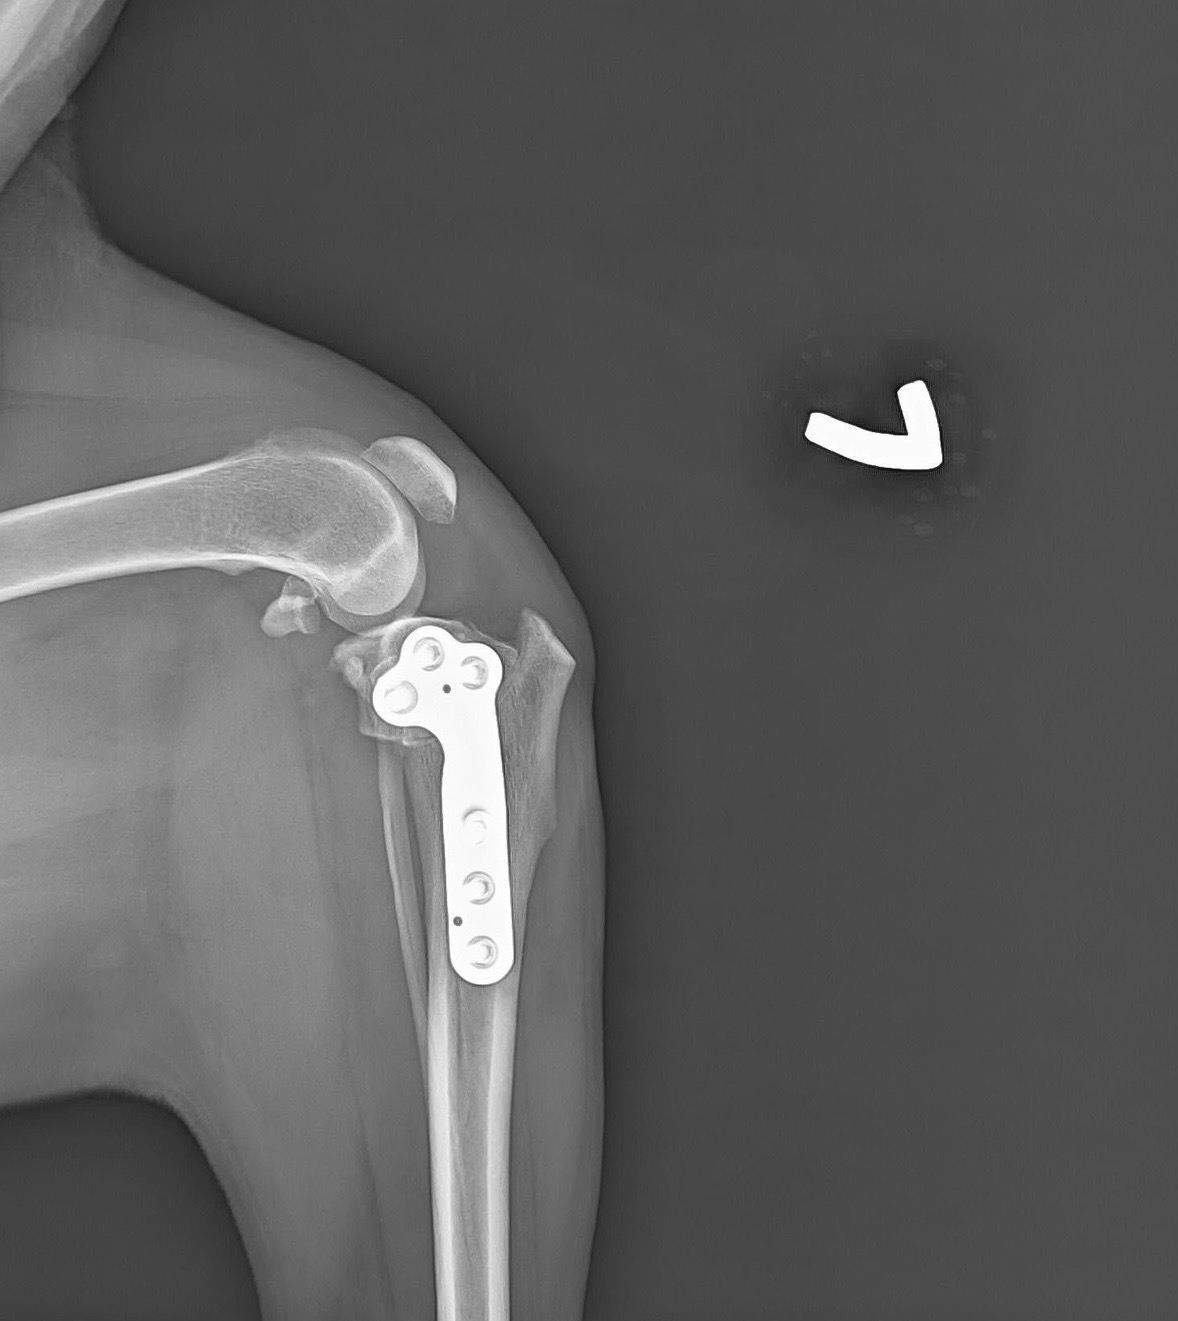

在脛骨進行環狀切割,藉由手術改變脛骨平台關節面的角度,並且使用TPLO骨板固定,使股骨不再向後滑動抑或是脛骨不再向前滑動,因此就不需額外使用線材做人工韌帶,也可避免人工韌帶可能發生的問題。

目前已術後一個月囉~嚕嚕步態一天比一天進步,回診追蹤狀況都很穩定。